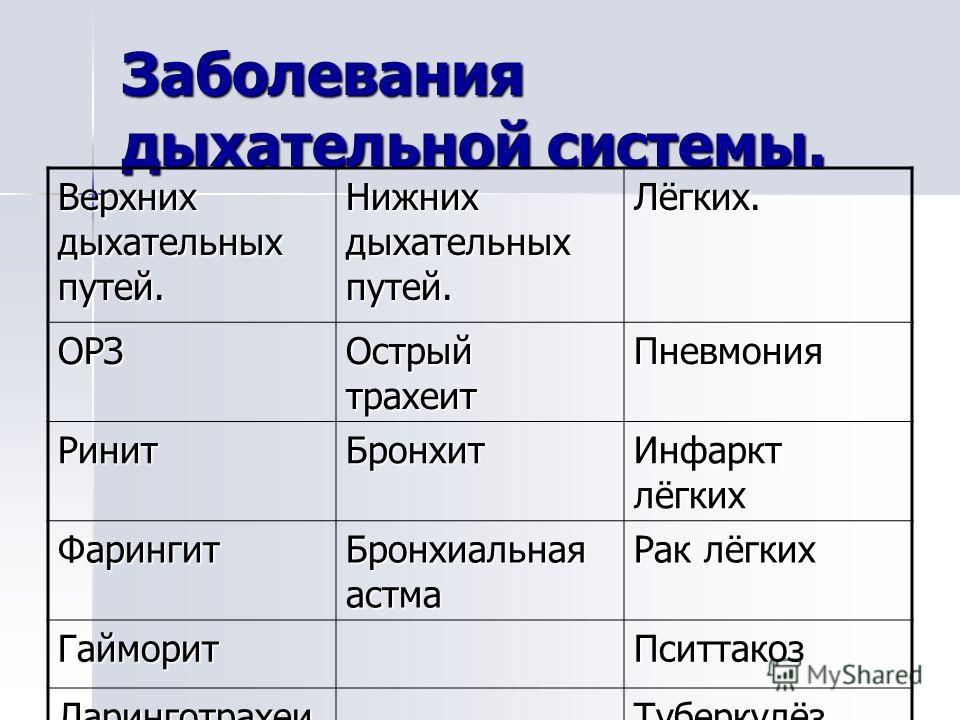

Дыхательная система выполняет жизненно важную функцию — обеспечение клеток организма кислородом и освобождение их от углекислого газа, являющегося конечным продуктом …

Дыхательная система . Дыхание как совокупность процессов, обеспечивающих поступление в организм кислорода и удаление углекислого газа . Органы, входящие в состав верхних …